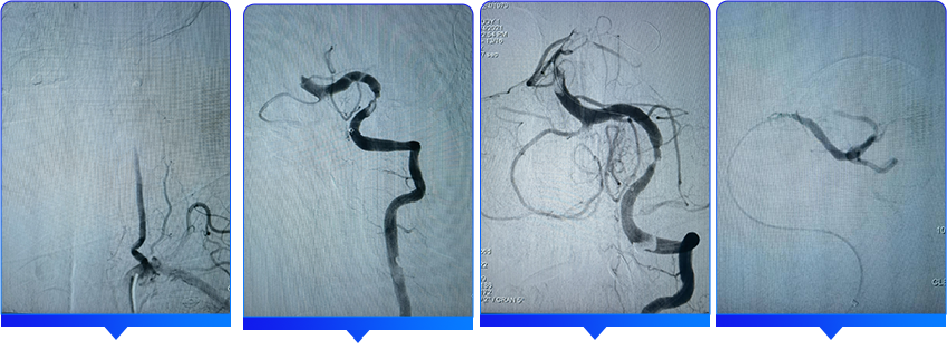

手术过程

采用seldinger穿刺法于右侧腹股沟下3cm处行股动脉穿刺,成功后置入8F动脉鞘。用5F猪尾巴造影管行主动脉弓上造影,为I型弓,两侧颈动脉显影良好,血流通畅,右侧椎动脉闭塞可能,左侧椎动脉血流缓慢。退出5F猪尾巴造影管后,利用泥鳅导丝置入5F单弯造影管分别置于双侧锁骨下动脉行选择性造影示:右侧椎动脉纤细,颅内段闭塞;左侧椎动脉为优势椎动脉,血流缓慢,V4段重度狭窄,狭窄约90%,基底动脉远端未显影,双侧大脑后动脉未显影。

退出单弯造影管,利用0.035in泥鳅导丝及单弯采用同轴技术将6F长鞘置于左侧椎动脉V2段,退出泥鳅导丝;置入0.014in微导丝和微导管在路图指引下缓慢通过左侧椎动脉狭窄处,微导管沿微导丝远端置于左侧大脑后动脉P2段,经微导管造影确认在血管真腔,利用300cm0.014微导丝交换退出微导管,沿微导丝置入3.0*20mm球囊在椎动脉狭窄段利用6atm预扩张;负压下沿球囊导管越过狭窄送入ACE抽吸导管,退出球囊导管,抽吸泵抽吸下抵近基底动脉闭塞近段,抽吸90s后缓慢回撤抽吸导管至体外,抽吸泵中可见多枚暗紫色血栓;复查造影:基底动脉中上段血栓影明显减少,基底动脉仍残留血栓;再次送入ACE抽吸导管至基底动脉近血栓处,抽吸约60s抽吸出多枚暗紫色血栓,继续抽吸120s,缓慢回撤抽吸导管至体外;复查造影:基底动脉完全再通,mTICI分级3级,远端未见栓塞及造影剂渗出;左侧椎动脉V4段残余狭窄约30%,观察5mm、10mm、30mm造影对比,狭窄处未见明显弹性回缩,血流维持良好。手术成功,退出6F长鞘。